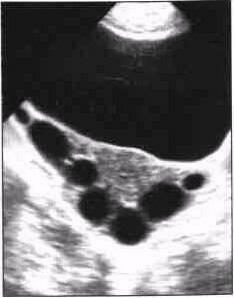

3. Абсцесс. В одной из параметральных областей лоцируется однокамерное жидкостное образование правильной округлой, реже овальной формы. Стенки плотные, толщина может достигать 8мм - результат воспалительной инфильтрации стенки трубы; контуры ров­ные, местами нечёткие и тяжистые за счет спаек. Размеры - не более 70 мм в диаметре. Структура содержимого неоднородная из-за мно­жественных мелких включений (фибрин, детрит), расположение ко­торых меняется в зависимости от положения пациентки: при гори­зонтальном положении эти включения равномерно распределяются в полости образования, при вертикальном положении - смещаются в нижнюю часть полости. Аналогичный эффект - п

Рисунок 3. Левосторонний пиосальпингс.

одвижность внутриполостных включений, достигается компрессией полости датчиком (особен­но ТВ). Этот симптом наблюдается при размерах патологического оча­га более 40 мм в диаметре. Форма включений либо вытянутая (длиной от 2 до 7 мм), либо они лоцируются как эхопозитивные точки. Плотность их низкая или средняя. Матка имеет обычный вид. У ряда больных на сторо­не поражения виден неизмененный яичник, оттеснённый в ту или иную сто­рону за счёт давления образования. Параметральные вены с двух сторон почти всегда расширены. Представленная УЗ-картина может быть расце­нена как ограниченный гидросальпингс с нагноением или, более точ­но, абсцесс маточной трубы (тубарный абсцесс).